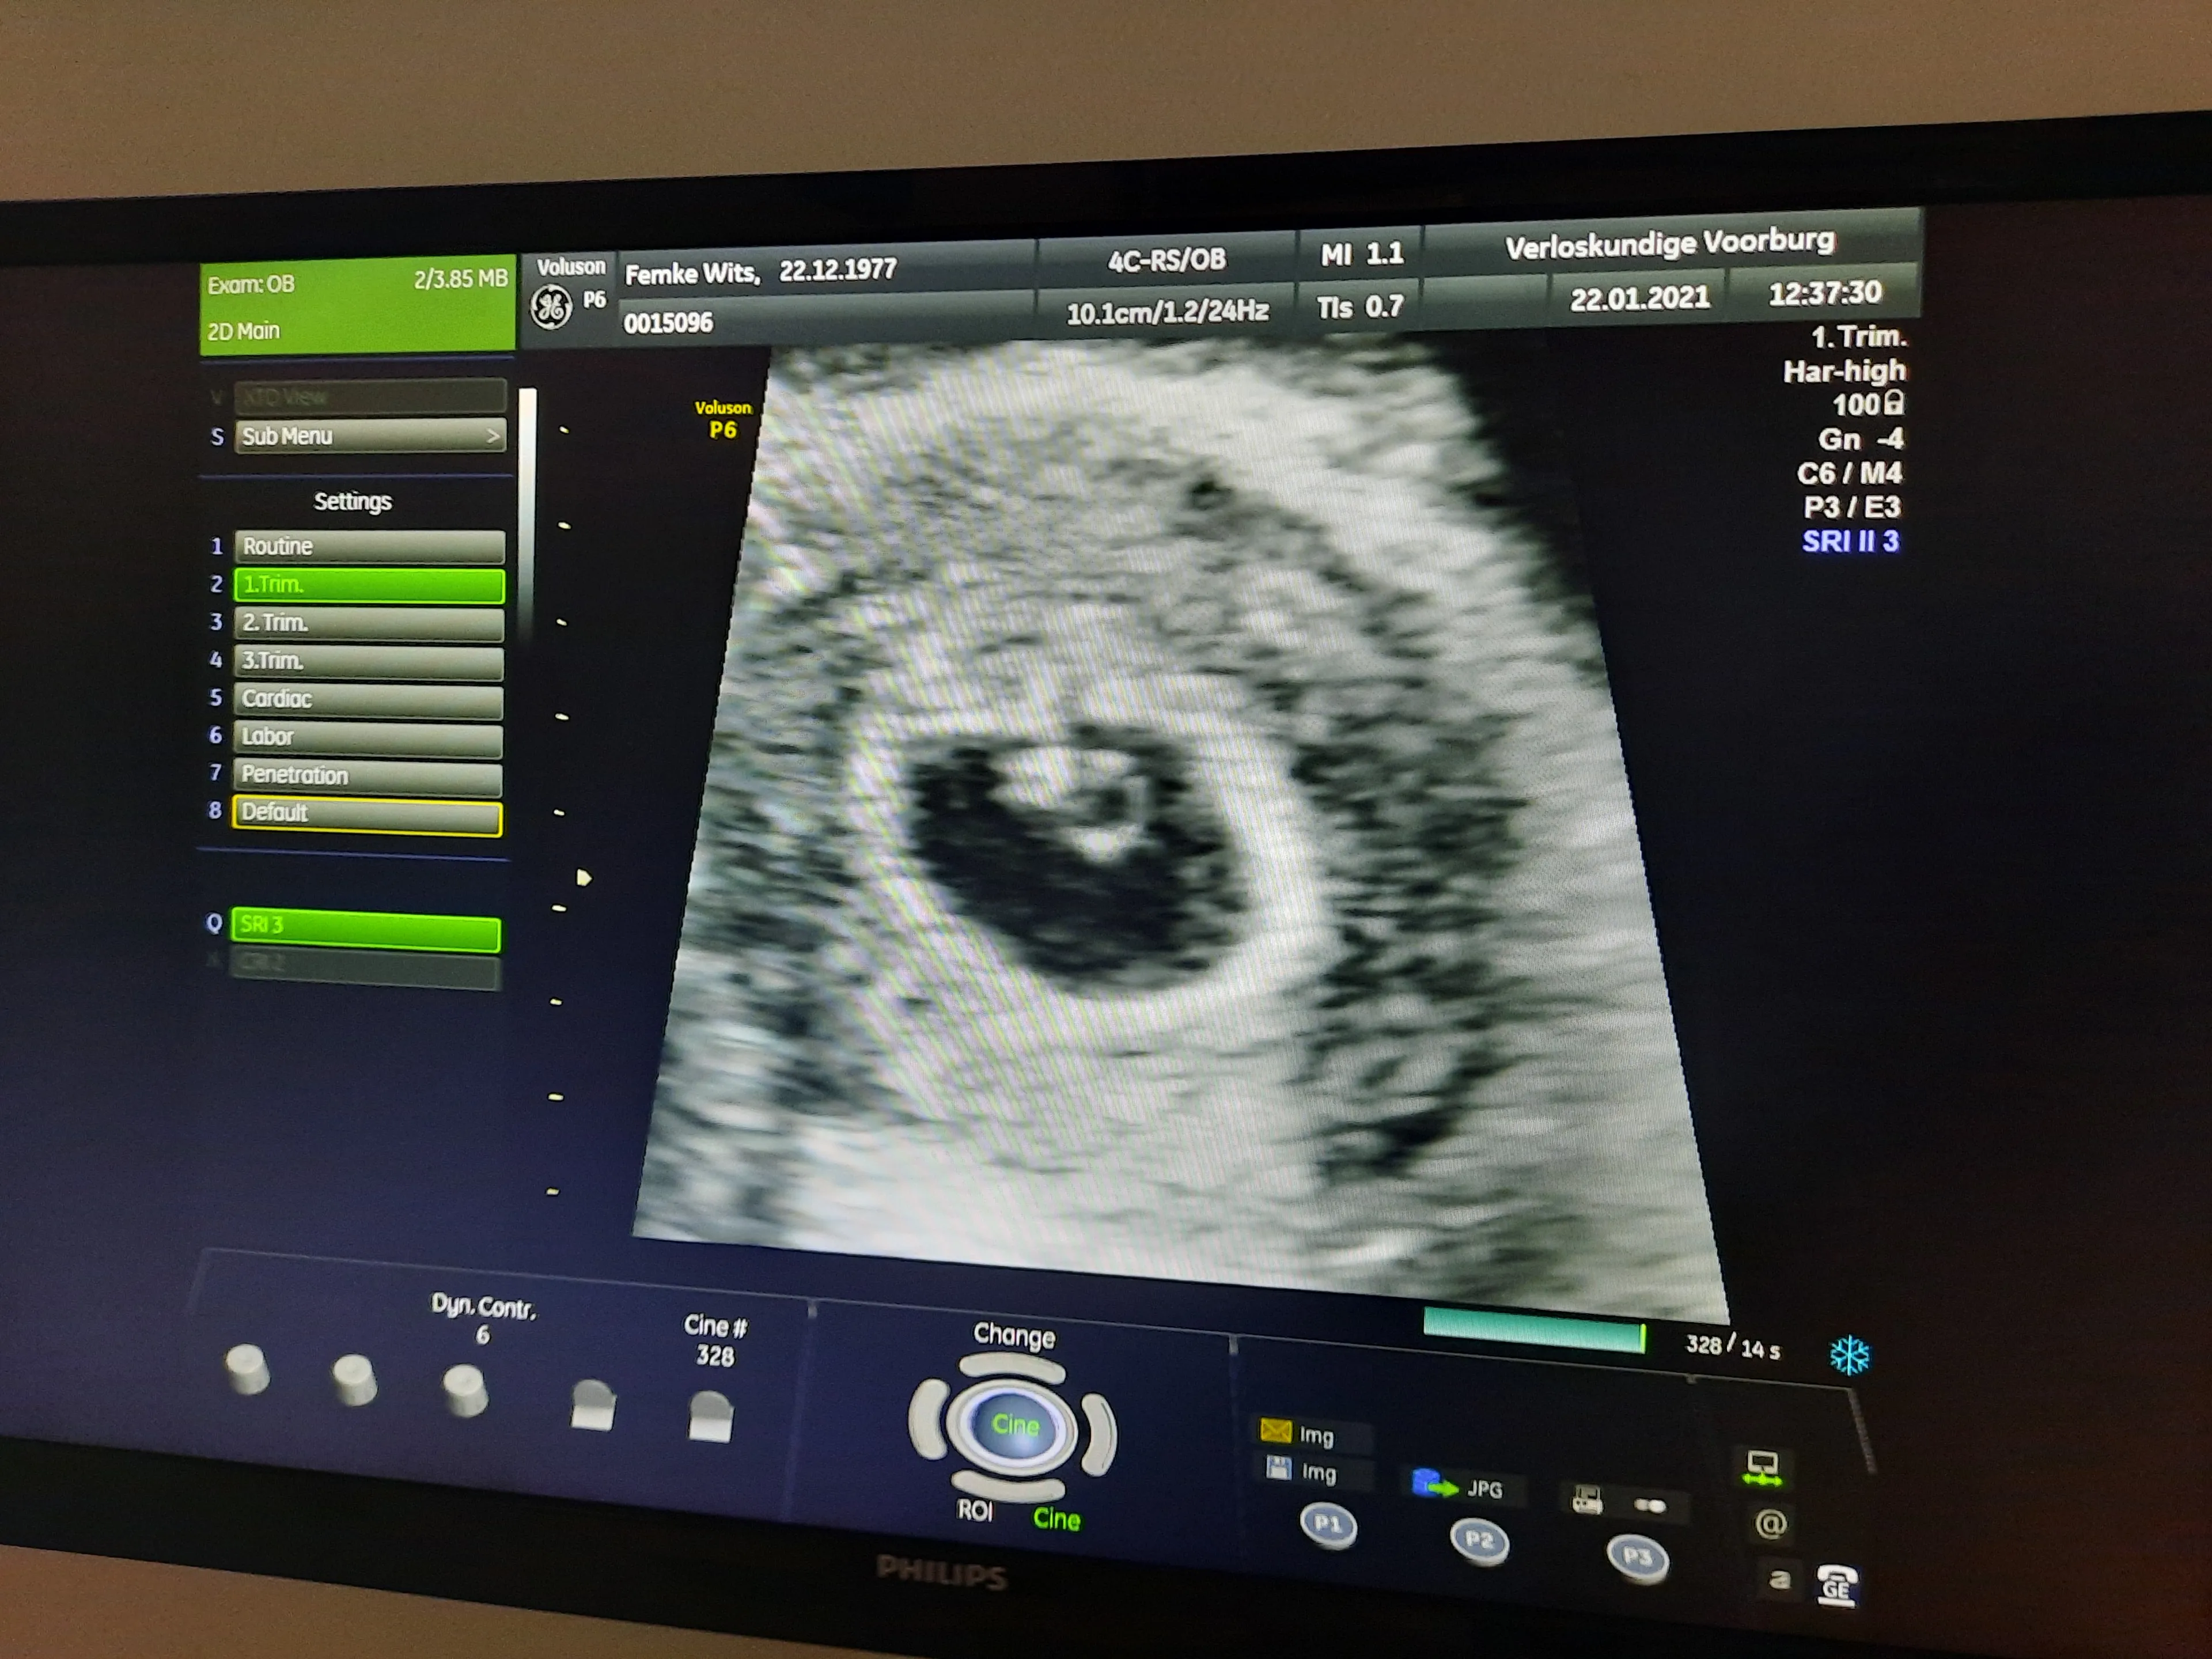

Maar als ze eind november 2020 naar het ziekenhuis gaan voor de eerste echo, is hun jubelstemming snel weer verdwenen. "De echoscopist vertelde ons heel bot dat het hartje niet klopte. We hadden er helemaal geen rekening mee gehouden dat het mis kon gaan. En we wisten dus ook niet hoe we met die boodschap om moesten gaan."

Twee weken later volgt er opnieuw een echo. "Die was weer spannend. Zou het allemaal nog goed gaan? En ja, ook nu zagen we het hartje kloppen." Bij de tien weken-echo in februari dit jaar krijgen Bas en Femke al iets meer hoop. "In het ziekenhuis zette de echoscopist het apparaat op Femkes buik. Ze zei: 'Ik zie het hartje kloppen.' Maar twee seconden later zei ze: 'Oh nee, toch niet.'"